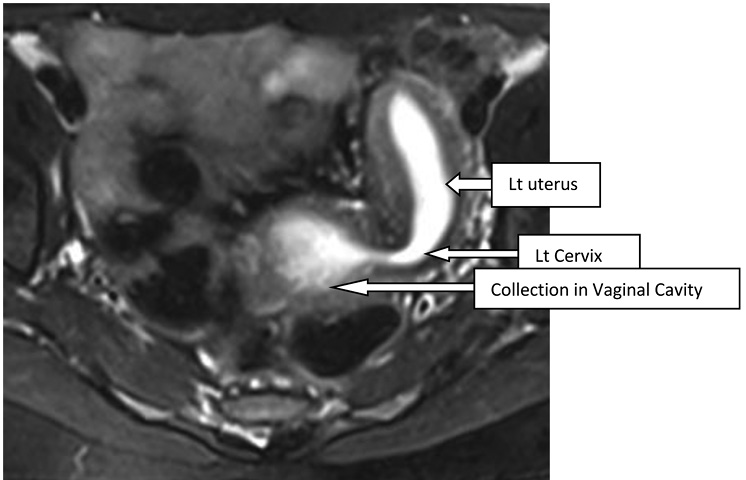

A 16-year-old unmarried girl presented to theoutpatient department of Obstetrics and Gynaecology, NEIGRIHMs Shillong with primary amenorrhoea and cyclical abdominalpain for 18months.The pain was moderate to severe in intensity, spasmodic in nature, and relieved by NSAIDs. She was a known case of juvenile diabetes mellitus. On general physical examination, the patient was thin built with the development of breast along with axillary and pubic hair, classified as Tanner’s stage 4. Her vitals were normal with normal findings on respiratory, cardiovascular, central nervous system examination. Her abdomen was soft and nontender with no mass palpable. After counseling and obtaining consent from the patient and her guardians, per vaginal examination was performed using one finger, which revealed an obstruction in the proximal part of the vagina(tranverse vaginal septum). A bulge was felt towards the left side of the vagina. Perrectal examination revealed a bulge in the upper part. She was subjected to radiological evaluation to look for other anomalies in the uppergenitourinary system.Transabdominal ultrasonography showed uterine didelphys with hematometra involving the right horn and normal renal system. She further underwent an MRI pelvis, which revealed two widely separated uterus with separate cervices. Both uteri were mildly distended with blood products, lesser in the left uterus with two cervices seen. There was evidence of a vaginal septum of 4mm thickness with a distended upper vaginal cavity and collapsed lower vagina. (Figure 1, 2) Her urinary system was normal.

Figure 2. T2 axial shows dilated endometrial cavity of uterus communicating with collection of upper vaginal cavity